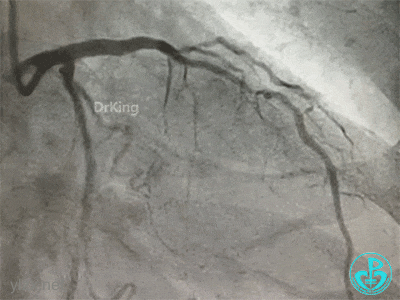

冠脉造影

右冠脉近中段不规则狭窄。短左主干中度狭窄,前降支开口严重狭窄,多功能造影导管推注造影剂时无反流,导管退出左主干开口造影发现左主干狭窄严重。

患者术中血压偏低,一度出现烦躁。及时IABP置入是手术能顺利完成的保障。术前的准备很全面,造影结果如下。